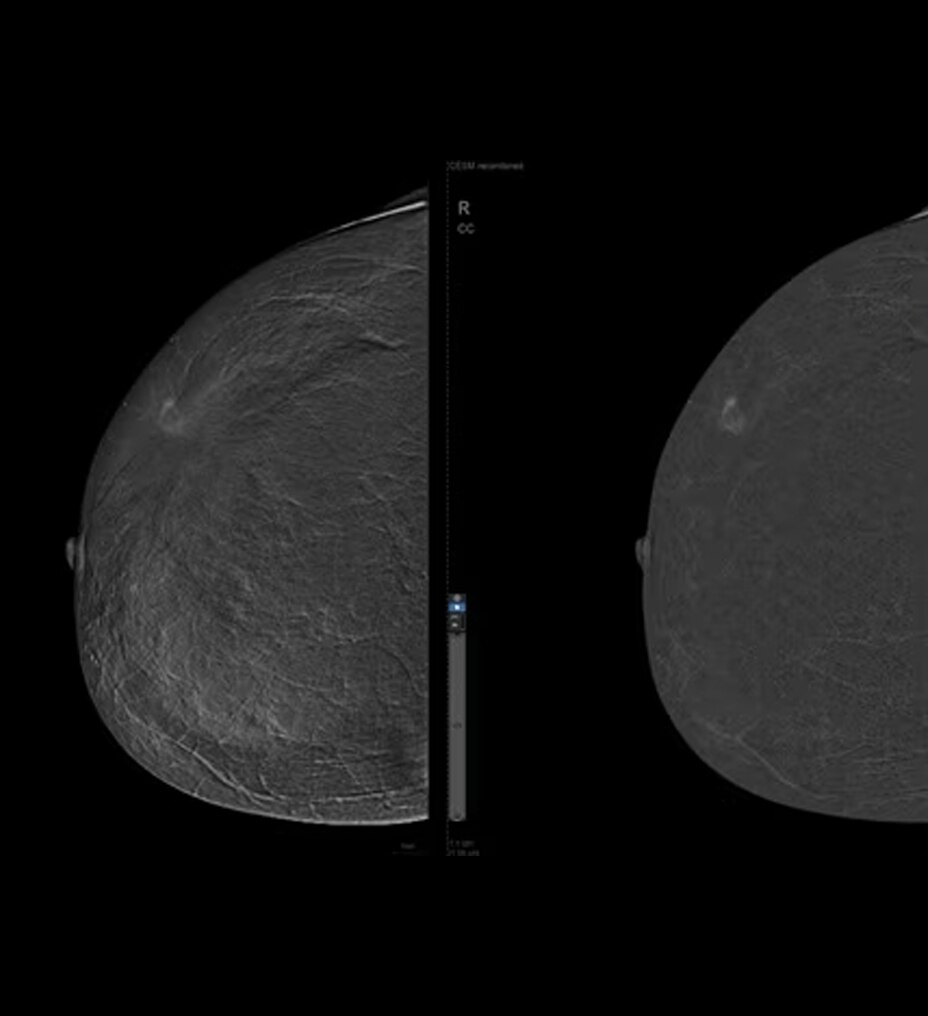

Mejore sus capacidades de diagnóstico con la innovadora cadena de adquisición de imágenes de Clarity, así como la calidad de sus imágenes en hasta un 30 %*

Cadena de adquisición de imágenes innovadora: la cadena de adquisición de imágenes de Clarity está formada por el detector del panel Atlas, el tubo de rayos X, el generador compacto de alta tensión y, de forma opcional, la reconstrucción ASiR. Ofrece una gran resolución espacial con ruido bajo y menos artefactos para satisfacer las diversas necesidades de los clientes en situaciones clínicas reales.

Diseño con eficiencia energética: la innovadora tecnología del detector ayuda a proporcionar una protección de su inversión a largo plazo al mismo tiempo que le ofrece resultados clínicos. El diseño del panel segmentado fabricado con avanzada tecnología de miniaturización y empaquetado reduce el consumo de energía y mejora el rendimiento térmico.